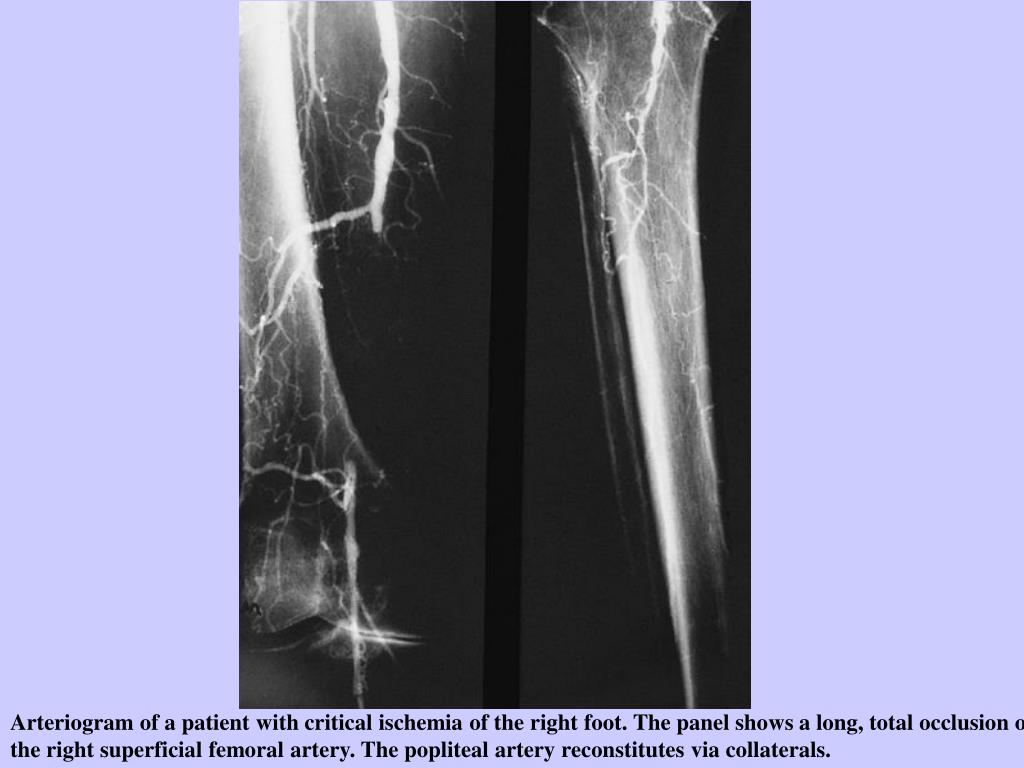

19. Arteriogram of a patient with critical ischemia of the right foot. The panel shows a long, total occlusion of the right superficial femoral artery. The popliteal artery reconstitutes via collaterals.